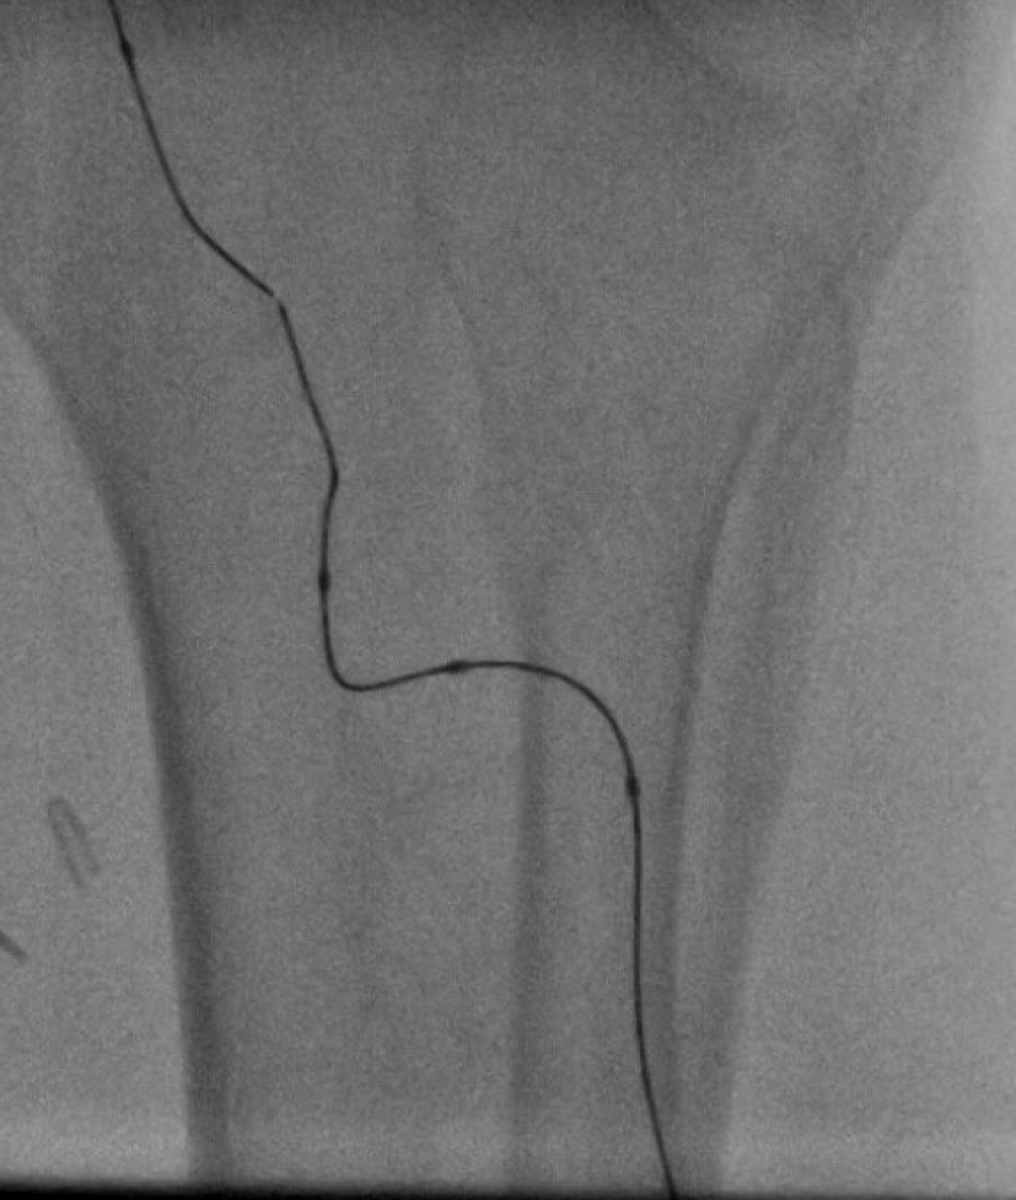

Xing occluded #BTK vessels w amplatz .035 / quickcross .035 helps maintain true lumen and quickly cross BTK CTO. @Abd_Alrifai @tlevin @chadialraies @RilioRiliol @DeanFerreraDO